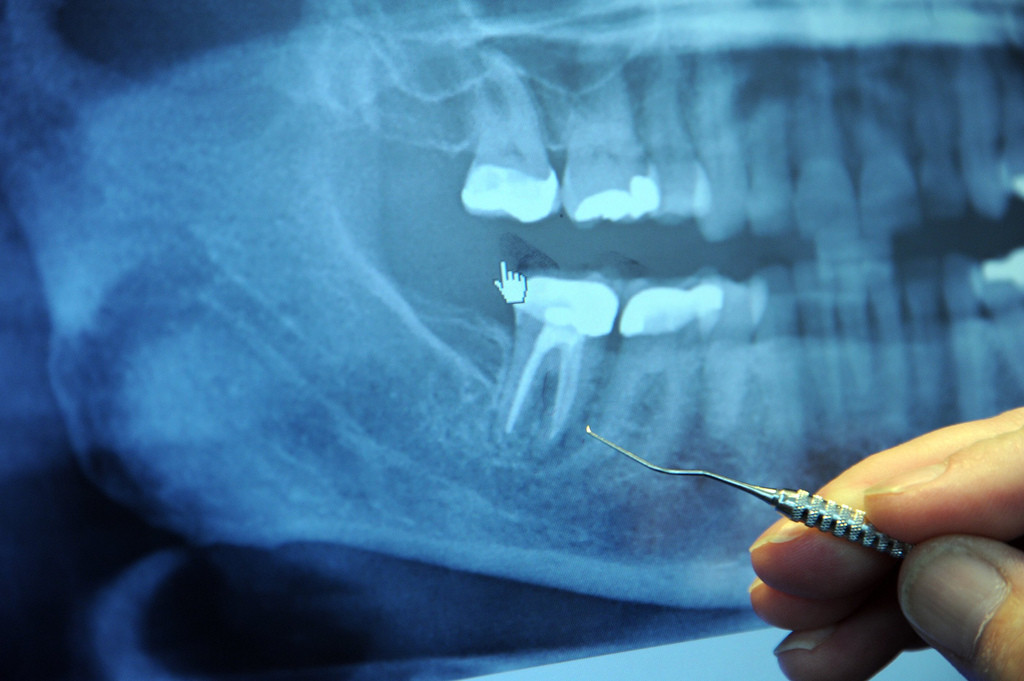

A filling is a dental procedure that involves a dentist cleaning away any decay from the tooth and then filling the space with a new material.

After injecting a numbing agent around the tooth, the dentist will then clean out the decayed area of the tooth, usually with a dental drill. They will then fill the space with gold, silver amalgam, a composite, or porcelain.